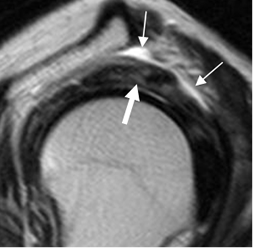

Fig 134. Tendinitis aguda del supraespinoso.

RM sagital en T2. Tendón supraespinoso hiperintenso, (Flecha gruesa), con líquido en la bursa SASD. (Flechas delgadas).